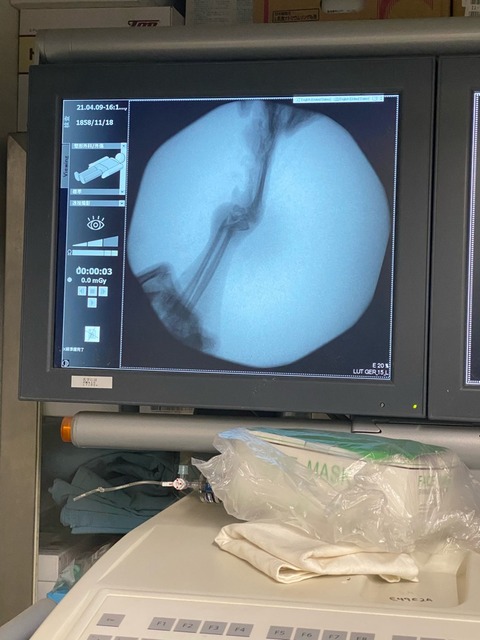

昨日のレスキューで連れてきたプードルの女の子は 左手がブラブラしていておかしいと思ったら

やはり骨折していました😱💦

以前に骨折して、そのまま放置された物だと言う事でした。

痛みは無いようですが ブラブラしています、

来週でも手術になります、

プレートの部品だけでも、高いです。💦